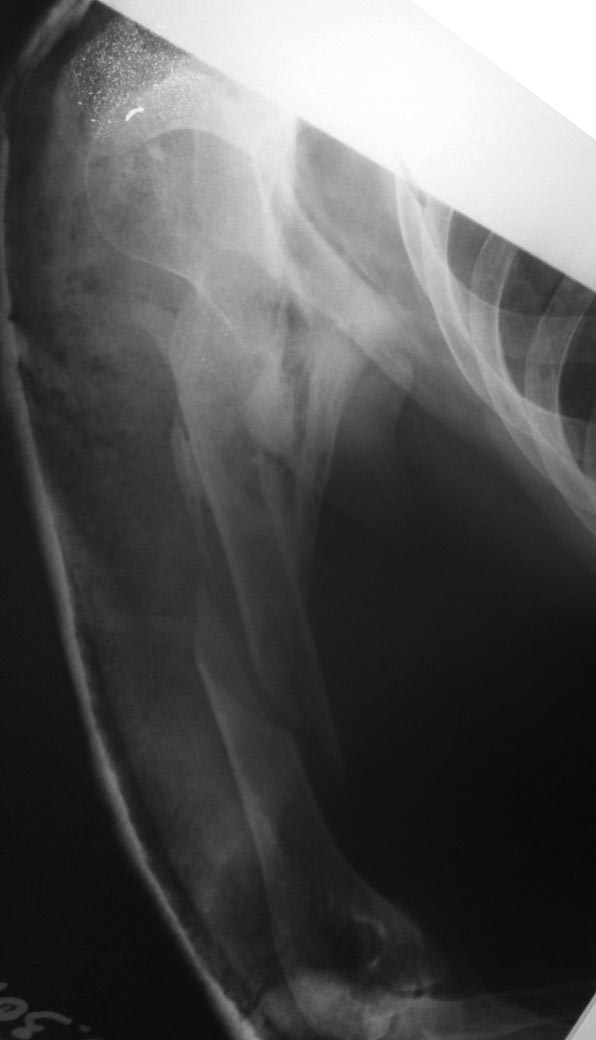

Больной в 2014 году находился на лечении в одной из Московских клиник. Диагноз: ТСТ.Перелом черепа Ушиб головного мозга. Диффузное аксональное повреждение. Длительное время находился на ИВЛ. Фрагментарный перелом плеча - консервативное лечение. Перелом голени - остеосинтез АНФ. На данный момент больной лежит в кровати. Речь понимает, отвечает односложно. Самостоятельно мог поворачиваться в пределах кровати. Поднимает нижние конечности, сгибание в коленных суставах и суставах стоп отсутствуют. При выполнении ЛФК - получен винтообразный перелом плечевой кости. У коллег прошу совета: есть мысль попробовать выполнить корригирующую остеотомию на уровне в\3 плечевой кости с последующим остеосинтезом переломов длинным гвоздем. Или выполнить остеосинтез ретроградным штифтом для дальнейшей возможности корригирующей операции, Т.к опыта таких операций нет.

добавлю снимки голени

Вчера несколько на эмоциях написал на форум. Более детально познакомился с пациентом. Является лежачим больным более 1.5 года, последние 3 месяца делал успехи в плане реабилитации(стал самостоятельно поворачиваться в постели, поднимает нижние конечности). Правая верхняя конечность отведение 80 гр, приведение полностью, небольшая сгибательная контрактура в локтевом суставе, сгибательная контрактура кисти и пальцев.. При выполнении ЛФК в домашних условиях 10.03.16г получен винтообразный перелом. Мягкие ткани - в подмышечной ямке кпереди по краю дельтовидной мышцы подкожно пальпируется в виде гребня костной плотности образование, кожа над ним фиксирована, а также в толще мышц избыточная костная мозоль. Первая мысль была сделать красивую рентген картинку. С учетом сниженной функциональной активности пациента, достаточно хорошей функции при таком сросшимся переломе правой верхней конечности, характером перелома(длинный винт). Выполнили сегодня остеосинтез перелома пластиной.